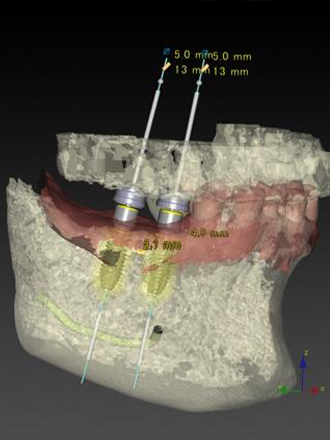

当院ではインプラントの手術前に必ずCT撮影を行い、骨の状態や重要な神経の位置の精査をします。この精密検査を行うことによりインプラントの埋める方向や深さの安全性を事前に確認することができます。

実際の手術を行う際にはサージカルガイドを用いることにより、事前に計画したインプラントの埋める方向や深さと誤差が無い正確な手術を行っております。

サージカルガイド

インプラント手術のシュミレーション